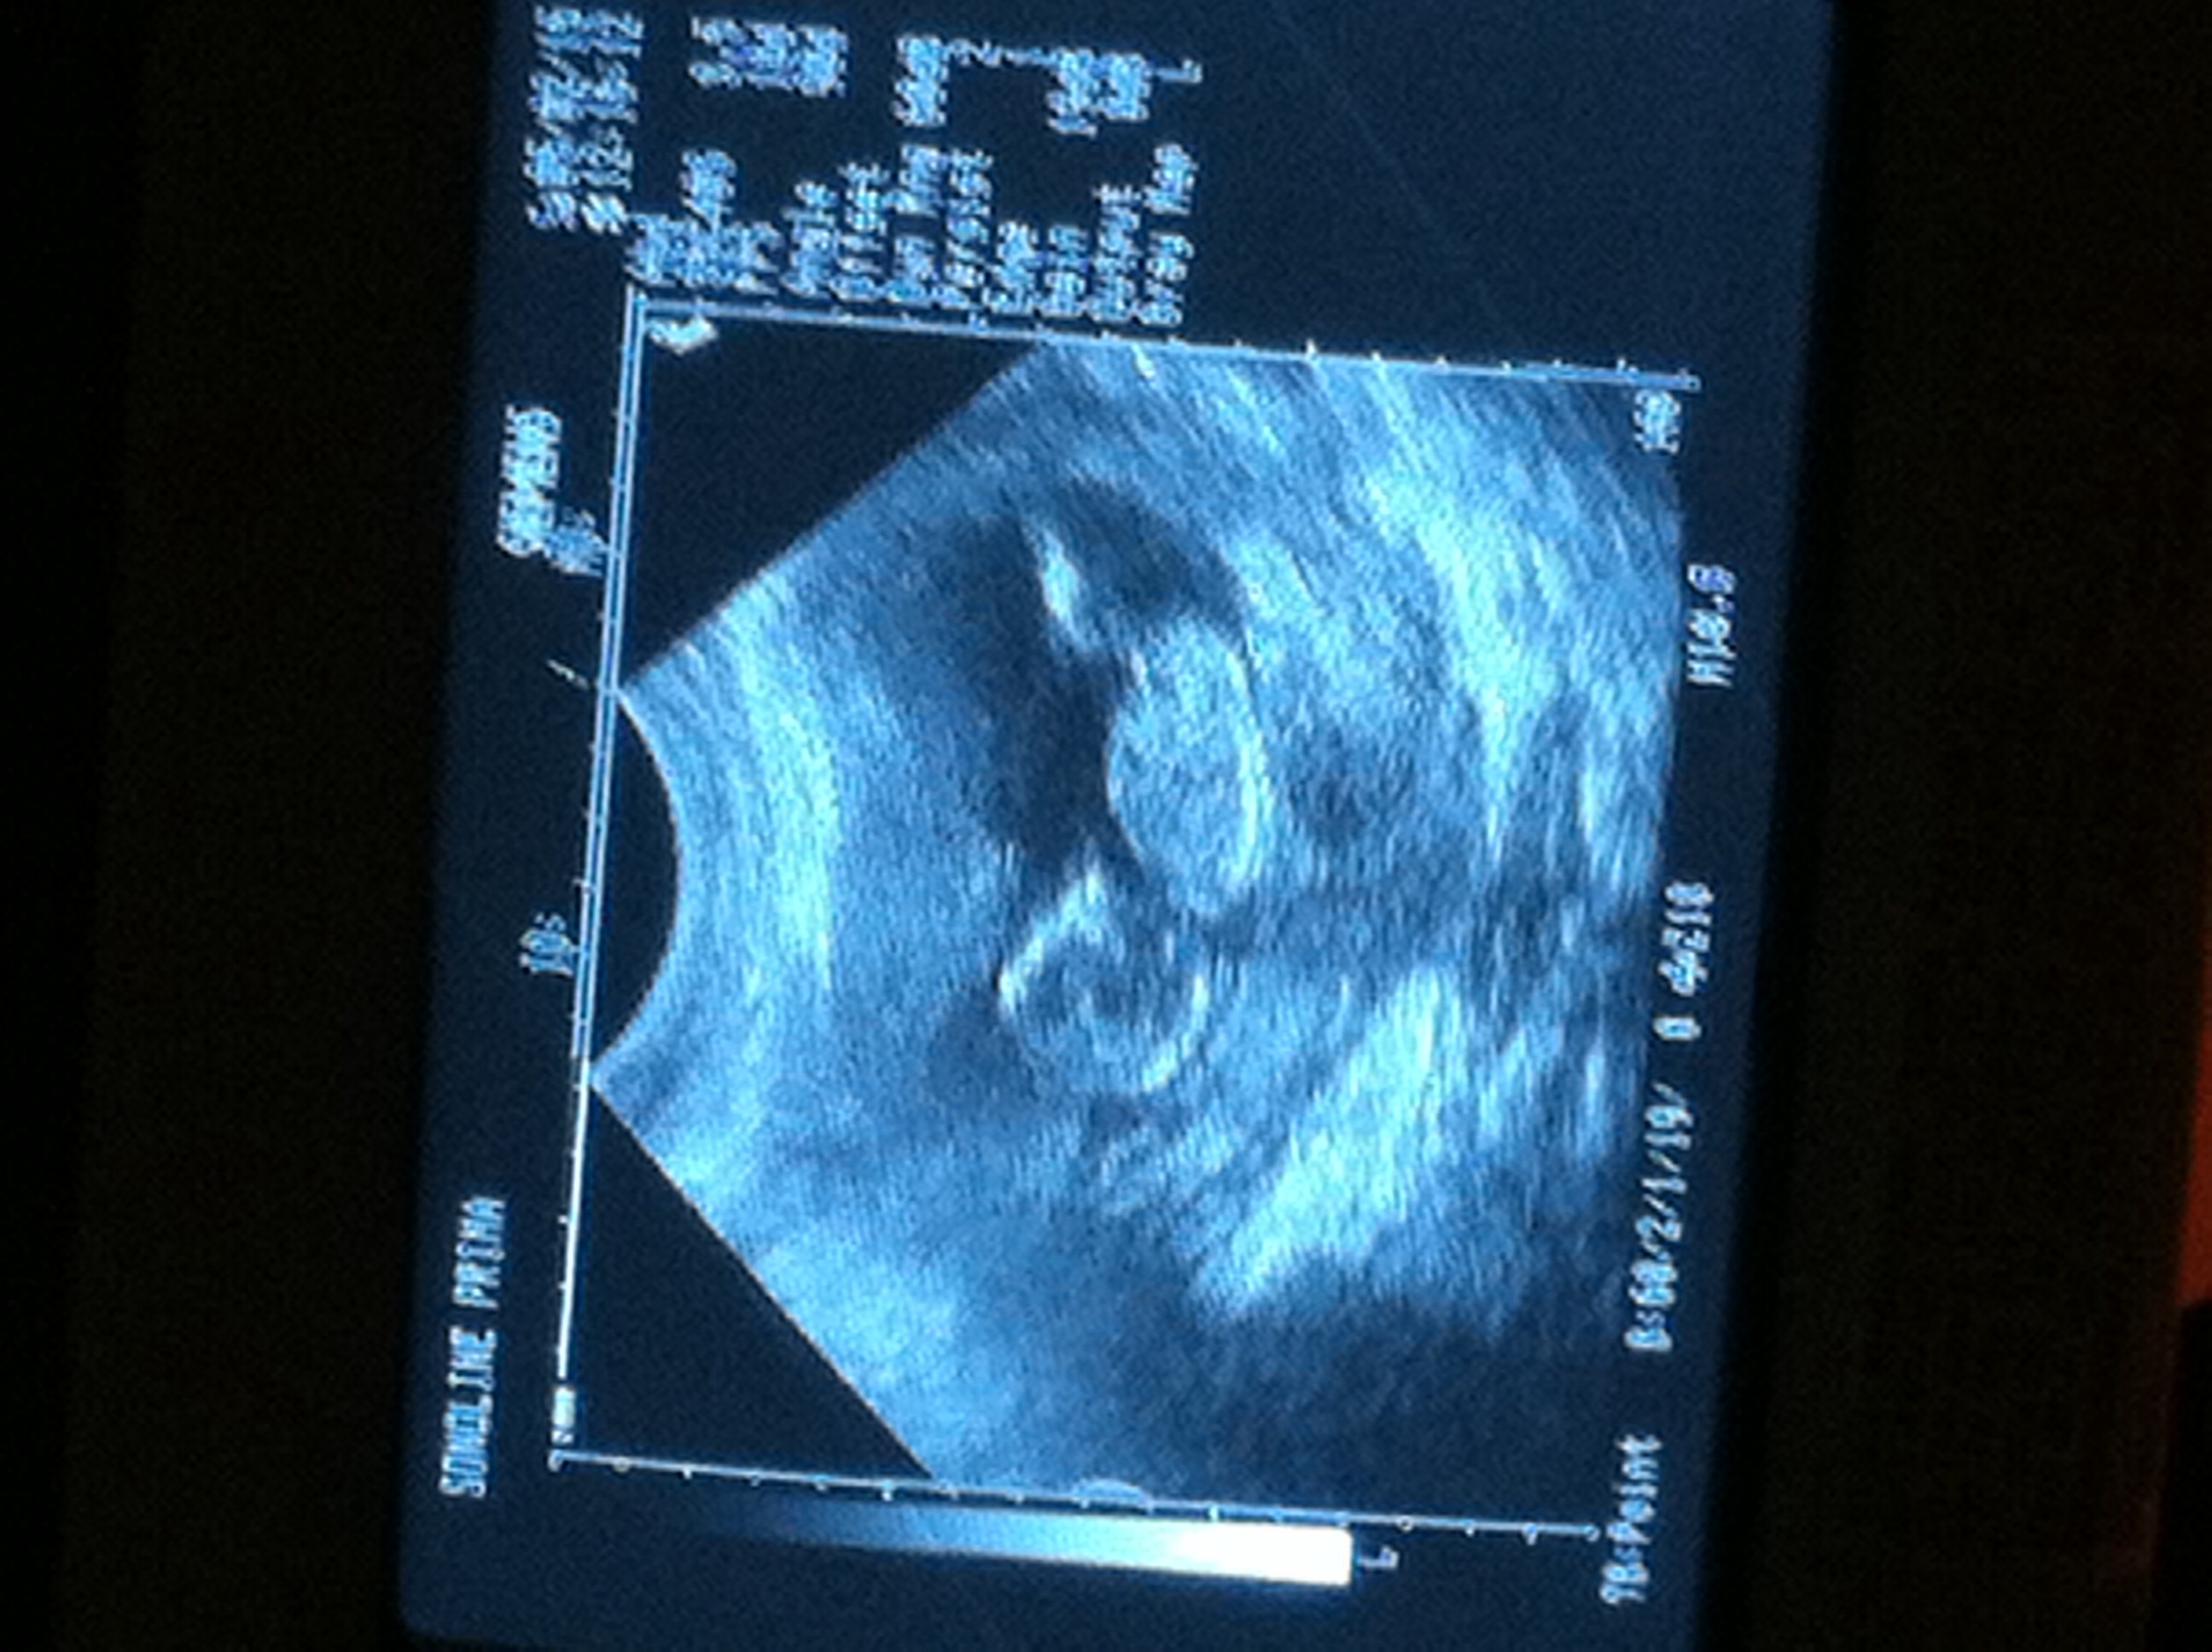

10 weeks 4 days yesterday.... Was waving and squirming all over... HR was 173.... So amazing... Get genetics test results and gender back in 7-10 business days!